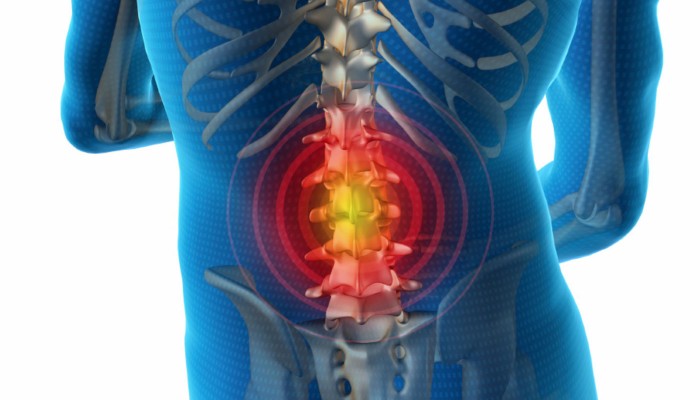

Среди многообразия межпозвоночных грыж, секвестрированная грыжа – одна из самых опасных разновидностей. Это заболевание характеризуется не только болью в позвоночнике. Имея его в анамнезе и не проходя соответствующее лечение, можно за короткое время превратиться в инвалида.

Секвестрация грыжи диска означает отделение полностью всего пульпозного ядра от самого диска. Чаще всего это происходит у пациентов после 40 лет из-за усиливающихся дегенеративно-дистрофических процессов в позвоночнике. Секвестрация часто неожиданна. Это объясняется тем, что межпозвоночная грыжа часто почти не даёт о себе знать.

Секвестрированных элементов может быть один или несколько. Они могут располагаться в любом отделе позвоночника – шейном, грудном, поясничном. Такие образования способны мигрировать, соприкасаться с оболочкой спинного мозга, передавливать нервы, вызывая множество неприятных, болезненных ощущений.

Такое состояние называется секвестрацией и представляет реальную опасность для спинного мозга. Поэтому почти 85% рекомендаций компетентных специалистов – оперативное вмешательство.

Секвестрированная грыжа диска l5-s1 характеризуется парезами или параличом нижних конечностей. Если не провести операцию, можно статьи инвалидом, так как ноги не будут работать. Примерно ¾ всех секвестраций встречается в районе диска l5-s1 и l4-l5, между поясничным и крестцовым отделами.Симптомы болезни:

Секвестрированная грыжа позвоночника, локализованная в крестцовом отделе, возникает реже, чем в поясничном отделе. Она провоцирует парезы и параличи ног, нарушение чувствительности кожи, угнетение работы органов малого таза. Такие симптомы обусловлены раздражением нервных окончаний конского хвоста – пучка нервных корешков спинномозговых нервов поясничного, крестцового и копчикового отделов позвоночника.

Секвестрация грыжи любого отдела позвоночника – опасное состояние.

Попадание инородного тела, которым является кусочек пульпозного ядра, в околопозвоночные ткани вызывает мощный воспалительный процесс. Он сопровождается отёком, который может полностью перекрыть кровоснабжение спинного мозга.